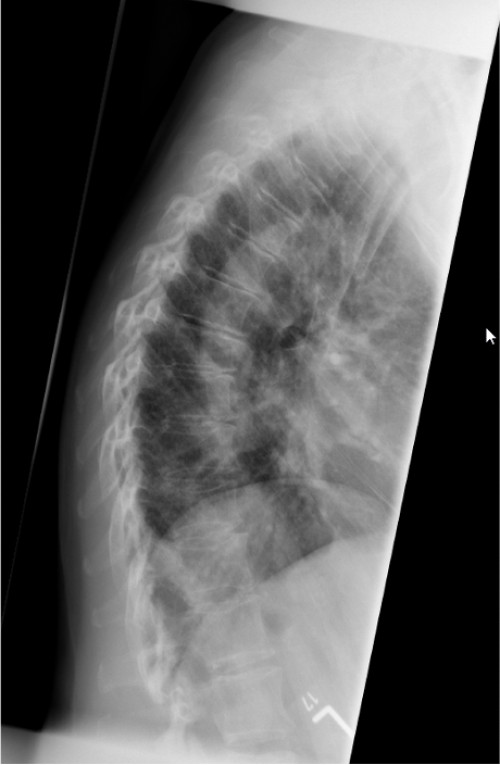

ICD: S22.04

Eine 66-jährige Patientin stellt sich in der Notfallambulanz vor und berichtet von einer Leiter gestürzt zu sein. Sie habe für ihren Enkel Lego-Spielzeug vom Dachboden holen wollen und sei dabei von der Leiter gerutscht. Sie sei auf ihren beiden Fersen gelandet und anschließend auf den Rücken gefallen. Der linke Fuß sei seitdem nicht belastbar, der rechte Fuß schon. Am rechten Fuß sei jedoch eine Schwellung im Bereich der Sprunggelenke sichtbar geworden.